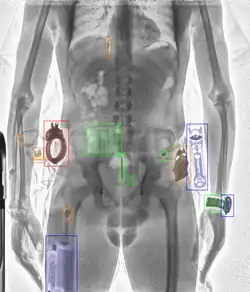

Сканеры, основанные на технологии проникающего рентгеновского излучения

Сканер представляет собой излучатель с одной стороны и детектор или массив детекторов с другой. Человек движется на конвейерной ленте между ними, либо стоящего человека с обеих сторон объезжает пара детектор/излучатель (по векторам вверх-вниз либо вправо-влево). Рентгеновские лучи проходят сквозь человека, позволяя получить детальное изображение. Современное программное обеспечение позволяет придавать цвета объектам разной плотности, но для сканирования человека пока эта технология не используется из-за повышенной дозы. Объекты определяются обученным персоналом и дополняются системами на основе технологий глубокого обучения.

Основное отличие проникающего рентгена от других технологий в том, что только он пока позволяет определить угрозы и контрабанду, которая находится не только на теле человека или в его одежде, но и внутри человека или спрятанную в естественных полостях тела. Разумеется, изображение, полученное на низких дозах не конкурирует со снимками диагностического качества медицинских аппаратов, но этого вполне достаточно, чтобы обнаружить объекты, не характерные для биологии человека.